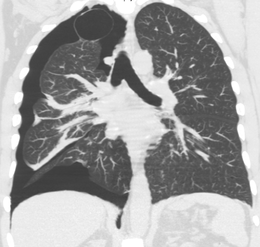

Image from a computed tomography (CT) scan of the chest. On the right (left side of the patient) there is a black area suggesting free air inside the chest

CT scan of the chest showing a pneumothorax on the person's left side (right side on the image). A chest tube is in place (small black mark on the right side of the image), the air-filled pleural cavity (black) and ribs (white) can be seen. The heart can be seen in the center.

Computed tomography

CT with the identification of underlying lung lesion: an apical bulla on the right side.

Computed tomography (CT, or "CAT scan") is not necessary for the diagnosis of pneumothorax, but it can be useful in particular situations. In some lung diseases, especially emphysema, it is possible for abnormal lung areas such as bullae (large air-filled sacs) to have the same appearance as a pneumothorax on chest X-ray, and it may not be safe to apply any treatment before the distinction is made and before the exact location and size of the pneumothorax is determined.[13] In trauma, where it may not be possible to perform an upright film, chest radiography may miss up to a third of pneumothoraces, while CT remains very sensitive.[16]

A further use of CT is in the identification of underlying lung lesions. In presumed primary pneumothorax, it may help to identify blebs or cystic lesions (in anticipation of treatment, see below), and in secondary pneumothorax it can help to identify most of the causes listed above.[13][17]